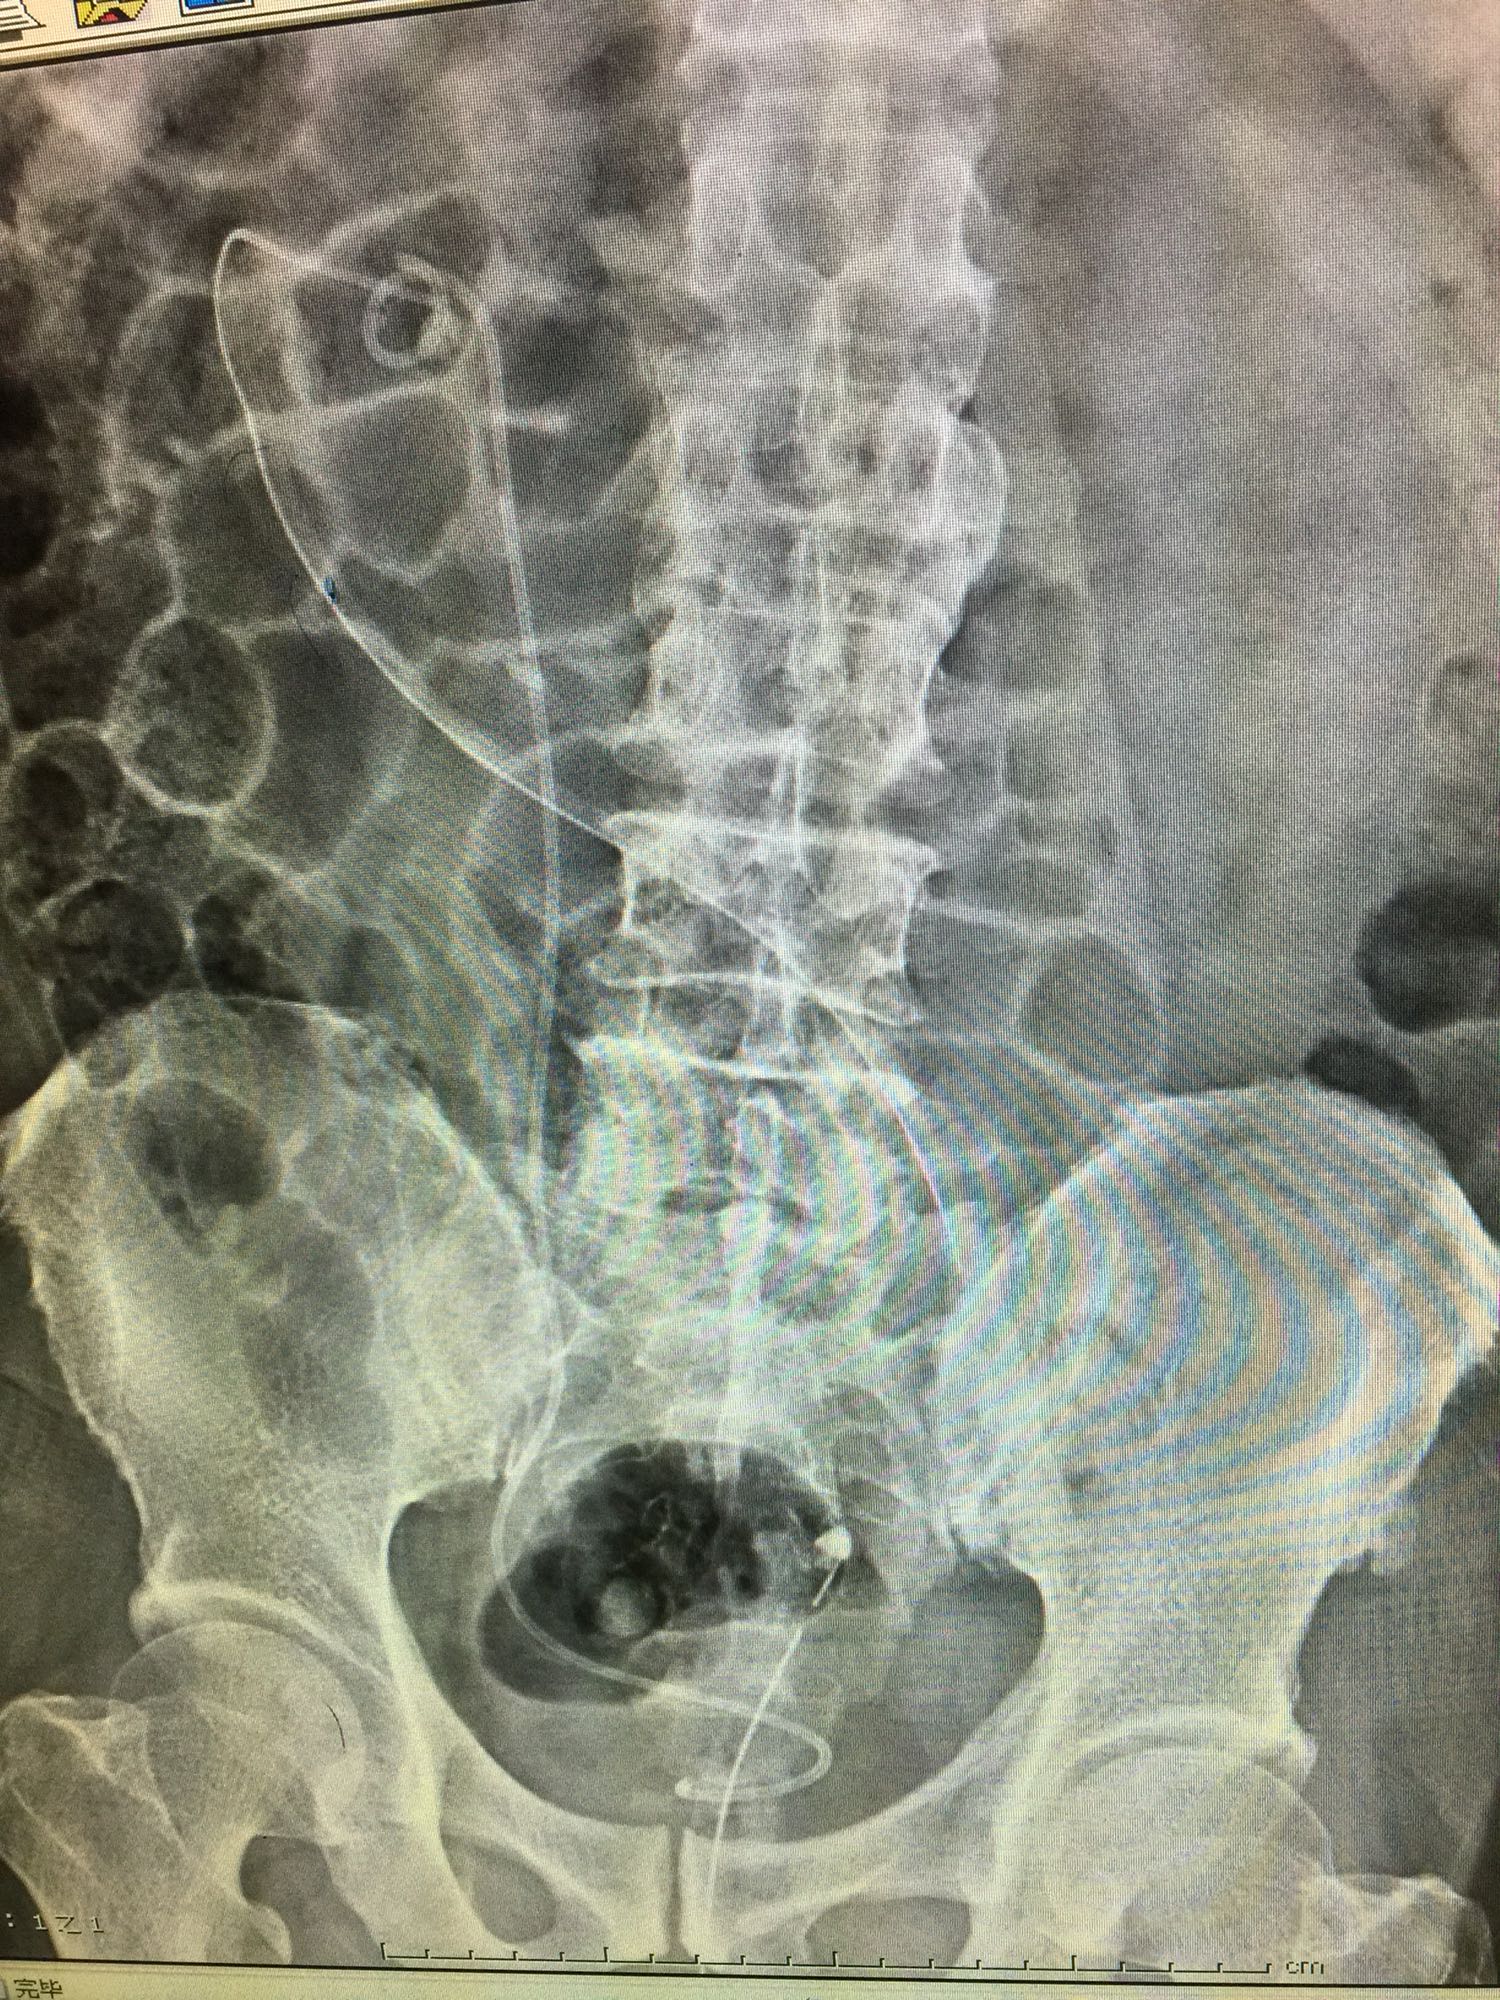

60岁男性 既往无高血压糖尿病等病史 检查发现右侧肾结石10年 10年前检查发现右侧肾结石,直径约1厘米,未给予正规治疗,近日来我院门诊,行彩超发现右肾多发结石,进一步治疗入院。

查体:双肾区无叩压痛,膀胱区无叩压痛,无叩浊,前列腺二度,质地中等,无压痛,无结节。CTU提示右肾铸型结石。ECTL 40,R14.5

右肾铸型结石 予以经皮肾碎石治疗,术后复查平片未见结石残留。